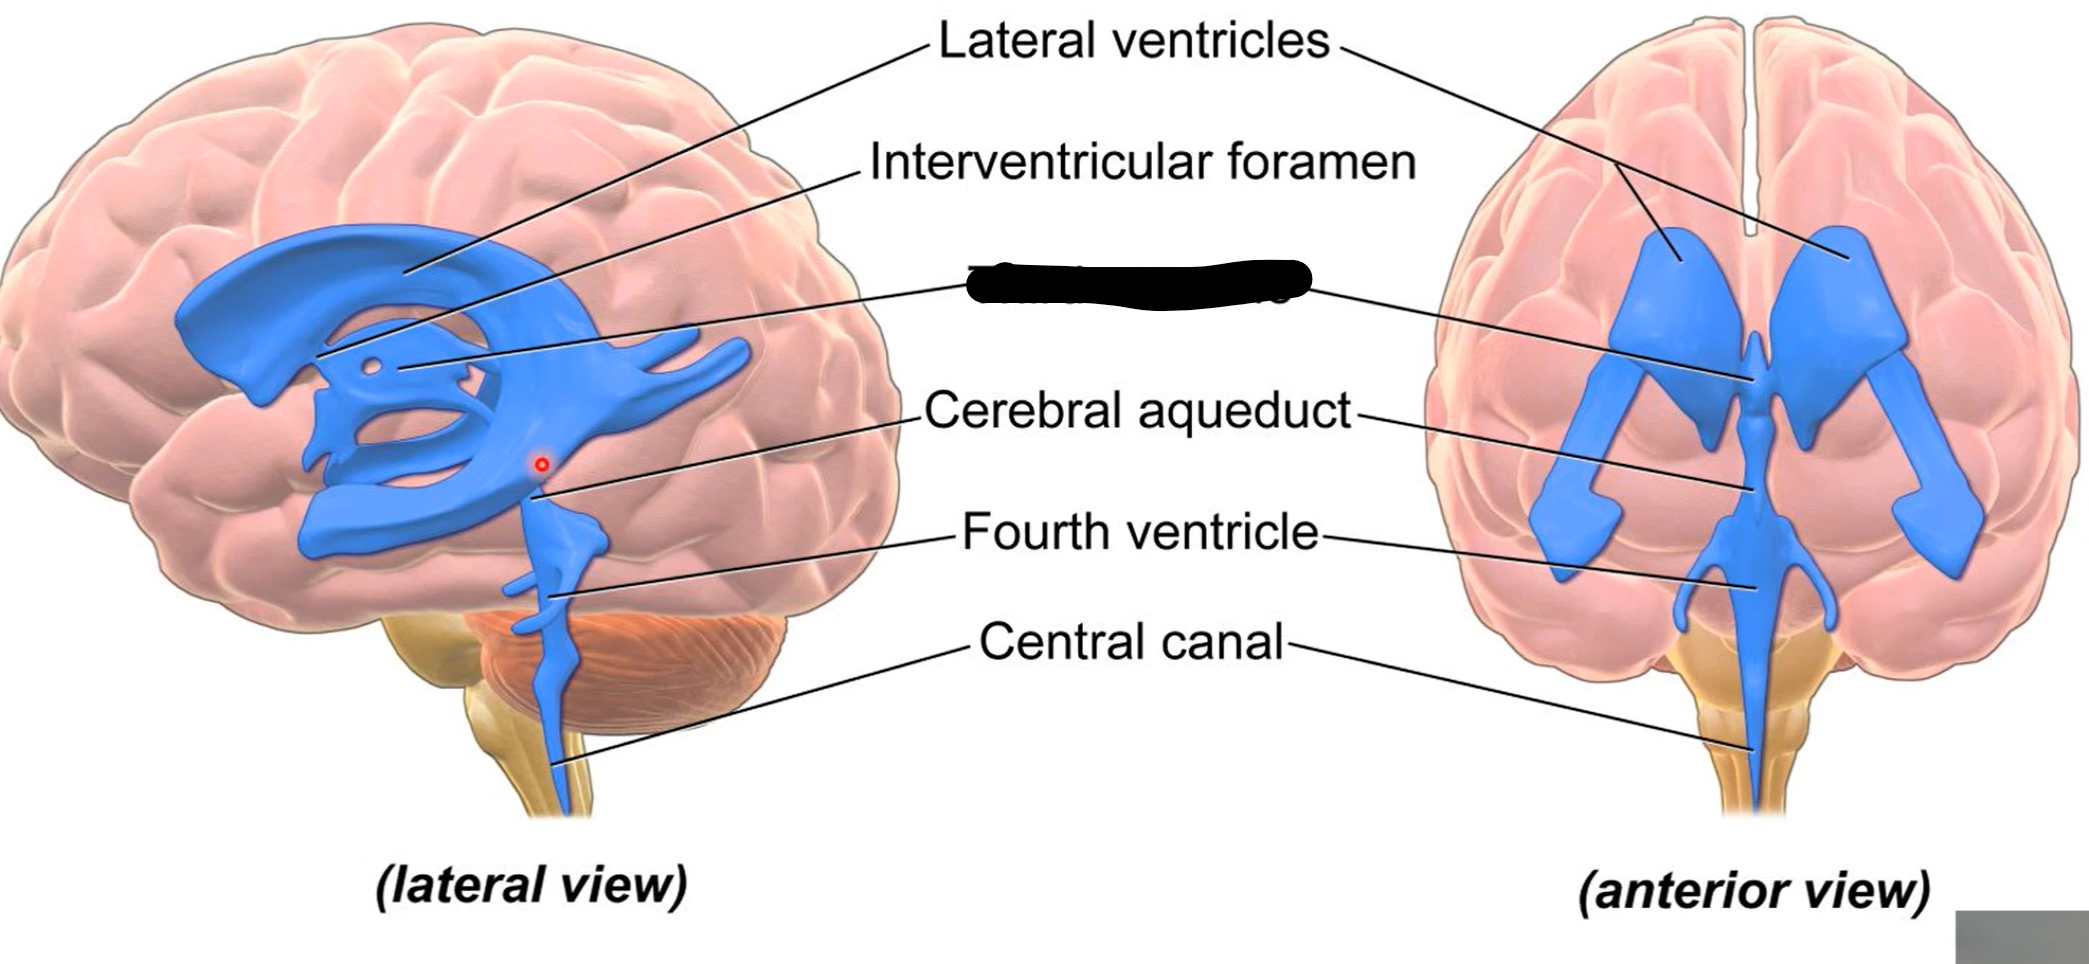

What do brain ventricles contain?

CSF

What makes CSF?

Choroid plexus

Where does CSF go from ventricles?

Subarachnoid space to enter circulation via arachnoid granulations

Choroid plexus

What carries CSF from 4th ventricle to subarachnoid space?

Median and lateral apertures

Arachnoid granulations

Lateral ventricles

Interventricular foramen

Third ventricle

Cerebral aqueduct

Fourth ventricle

Central canal